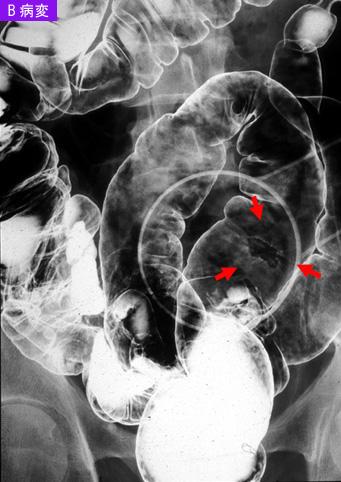

疾病(病理主体)的分类恶性上皮性肿瘤/腺癌

部位(按器官分)大肠/乙状结肠

检查方法X线

肿瘤的肉眼分类0型(表在型)/IIa型(IIa+IIc)

肿瘤最大直径15~19

肿瘤的深度sm

多发性肿瘤(同一器官)有(同时性)